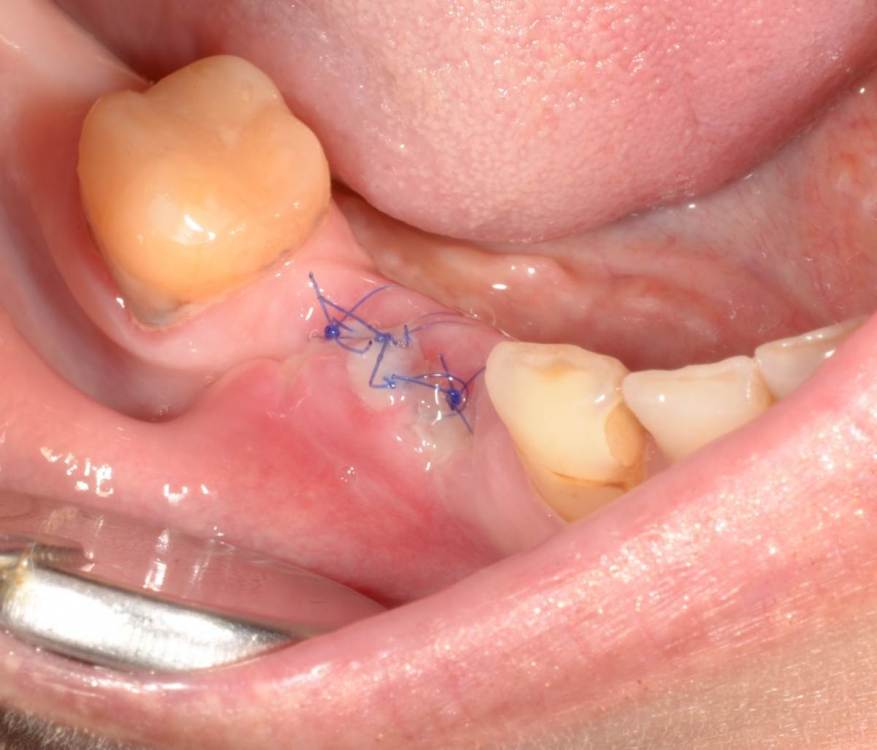

Большой Зеленый Опубликовано 27 мая, 2022 Поделиться Опубликовано 27 мая, 2022 Через 9 лет. Есть немного рецессии.. 2 Ссылка на комментарий

pit Опубликовано 27 мая, 2022 Поделиться Опубликовано 27 мая, 2022 4 часа назад, Большой Зеленый сказал: Через 9 лет. Есть немного рецессии.. Это связано исключительно с вестибулярной позицией импланта. Это как раз к вопросу про те минимальные 2мм до вестиболярной стенки, вне зависимости есть она или ты ее создаешь. Ссылка на комментарий

Большой Зеленый Опубликовано 28 мая, 2022 Поделиться Опубликовано 28 мая, 2022 12 часов назад, Женька сказал: @Большой Зеленый это вроде ваш старый кейс? напомните пожалуйста, тут присыпка+мембранинг вестибулярно и вестибулярным лоскутом слегка послабленным всё закрыли? Да все так и есть как Вы и описали. Работе почти 10 лет. Присыпка мп3 от остеобила сверху "ильгамовская" губка . Считаю что результат вполне удовлетворительный. Рецессия обусловлена как уже сказали выше вестибулярным положением импланта ,ну и недозаглублен чуток. Ссылка на комментарий